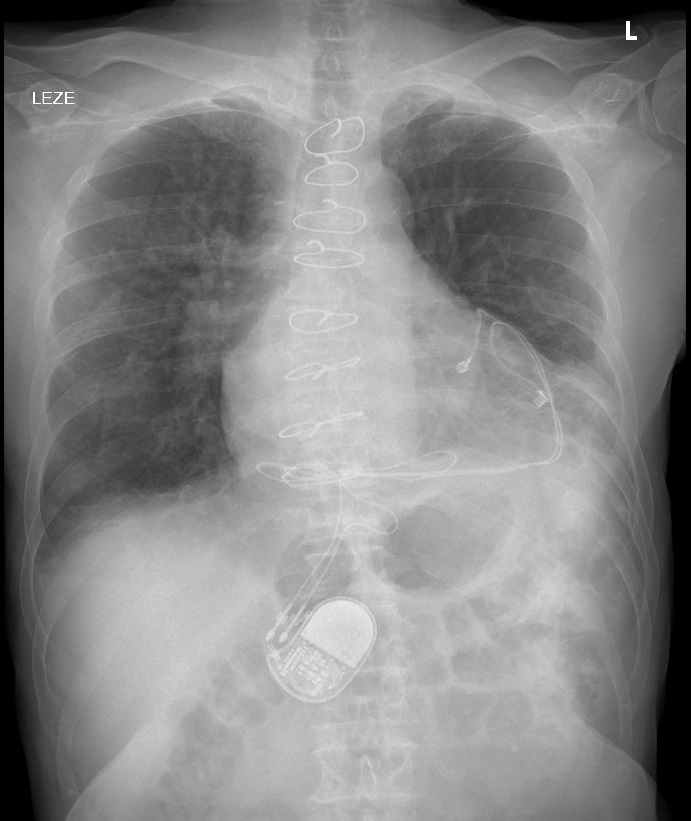

Chest X-ray

This lumbar spine DXA scan shows an artifact over the L1 vertebral body. After careful assessment of the DXA image, a pacemaker was identified and confirmed with evaluation of the prior chest x-ray images. BMD was measured in a male patient, as part of comprehensive follow-up for osteoporosis and endocrine abnormalities in post-heart transplant patients. L1 was omitted because of the overlying artifact. L4 was omitted because of degenerative change and discordance.

External or internal artifacts, such as bra wires, body jewelry, spinal fusion hardware, radiopaque medications are commonly encountered in DXA images. Because pacemakers are usually placed under collarbone, they are not seen on DXA image. However, in adults with heart surgery and children, often pacemakers with epicardial lead placement are used. Epicardial pacemakers are inserted in retrocostal, subxiphoid or subrectus location and can distort DXA measurements in this specific population.